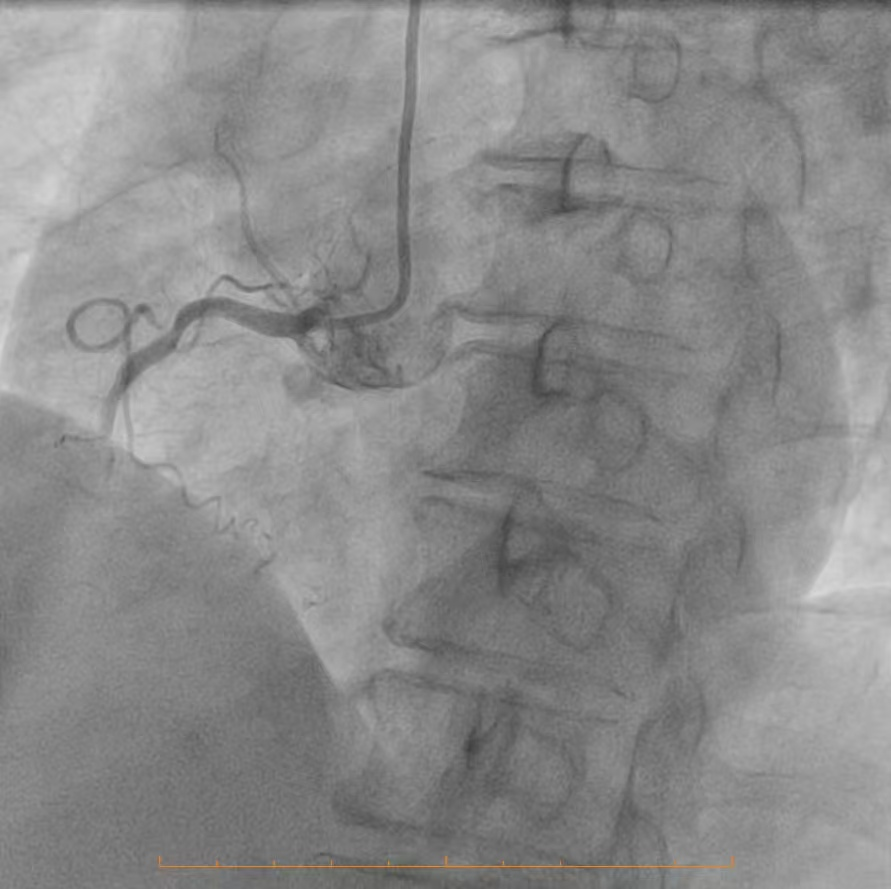

精准研判,明晰战场:冠脉造影揭示严峻挑战

为了制定万无一失的手术方案,必须首先精准“侦察”敌情。团队为患者进行了冠状动脉造影检查,结果清晰地揭示了心脏血管内严峻的形势:造影显示,患者冠脉分布呈右优势型。左主干未见明显异常,这为手术提供了一个相对安全的基础。然而,危机四伏:前降支——心脏最重要的供血血管之一,其近段开口处及以下部位存在约80%的严重狭窄,而中段更是出现了高达90%的极重度狭窄,血流已岌岌可危,是引发严重心绞痛甚至心肌梗死的主要“罪犯血管”。回旋支近段亦存在约60%的狭窄,影响了侧壁的血液供应。情况最为凶险的是右冠脉,其近段有50%的狭窄,而中段以下已经完全闭塞,远段仅能依靠来自左冠脉系统的微弱逆灌注血流勉强维持,这解释了患者为何症状如此严重,生命时刻受到威胁。

冠脉造影影像3

这份造影报告,如同一张错综复杂、险象环生的“作战地图”。前降支的多处严重狭窄与右冠脉的慢性完全闭塞,共同构成了一个高危、复杂的冠心病诊断。传统的开胸搭桥手术风险极高,而介入治疗同样面临着巨大的技术挑战,尤其是在开通慢性完全闭塞病变(CTO)时,犹如在险峻的峭壁上开路,对术者的技术、经验、耐心和心理素质都是极致的考验。